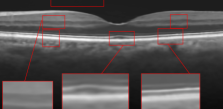

The effect of the overlap of the patches on the final output of the algorithm has been investigated in the next simulation. For this purpose, the outputs of the proposed approach for the situations and have been compared. When , the patches have no overlap. The resulting higher resolution OCT images for each situation have been illustrated in Fig. 8. Visual comparison in addition to the PSNR and SSIM for each image, show that using patches with overlap, we can increase the performance of the algorithm and consequently improve the quality of the output image.

Reference image

Using patches without overlap

Using patches with overlap